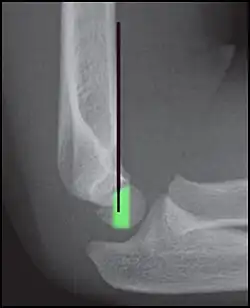

Anterior humeral line - It is a line drawn down along the front of the humerus on the lateral view and it should pass through the middle third of the capitulum of the humerus.[9] If it passes through the anterior third of the capitulum, it indicates the posterior displacement of distal fragment.[8]

Anterior humeral line (black line), with normal area passed on the capitulum of the humerus colored in green in a 4 year old child.[9] -

The anterior humeral line is not reliable in children with sparse ossification of the capitulum, such as in this 6 months old child.[9]